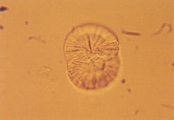

Особенности Цистиновые кристаллы бесцветные, характерной гексагональной формы с равными или неравными сторонами (рис. 25-26). Они могут появляться одиночно, но чаще в виде агрегатов. Их определение требует уменьшения световой интенсивности, так как они тонкие. Цистиновые кристаллы чаще всего формируются в концентрированной кислой моче. Формирование явной щелочной мочи, как следствие инфекции или контаминации уреазообразующими микробами, может способствовать образованию цистиновых кристаллов. Добавление ледяной уксусной кислоты после замораживания и центрифугирования может улучшить определение типичных кристаллов в образцах щелочной мочи. Цистиновые кристаллы нерастворимы в уксусной кислоте, спирте, ацетоне, эфире и кипящей воде. Они растворимы в аммиаке и соляной кислоте. Интерпретация Цистиновая кристаллурия ненормальный феномен. Цистиновые уролиты могут развиваться у собак и кошек с метаболическим расстройством цистинурии. Однако, не у всех пациентов с цистенурией развиваются цистиновые уролиты (см. обсуждение магний аммоний фосфатной и мочевокислой кристаллурии для детальной дифференциации цистиновых кристаллов от струвитов и кристаллов мочевой кислоты). Рис. 25. Микрофотография цистиновых кристаллов в мочевом осадке 2- летнего кобеля английского бульдога с цистиновыми камнями в мочевом пузыре (не окрашено, увеличение Х 250).

Рис. 26. Сканированная электронная микрофотография кристаллов, описанных в рис. 25 (увеличение Х 1,980).